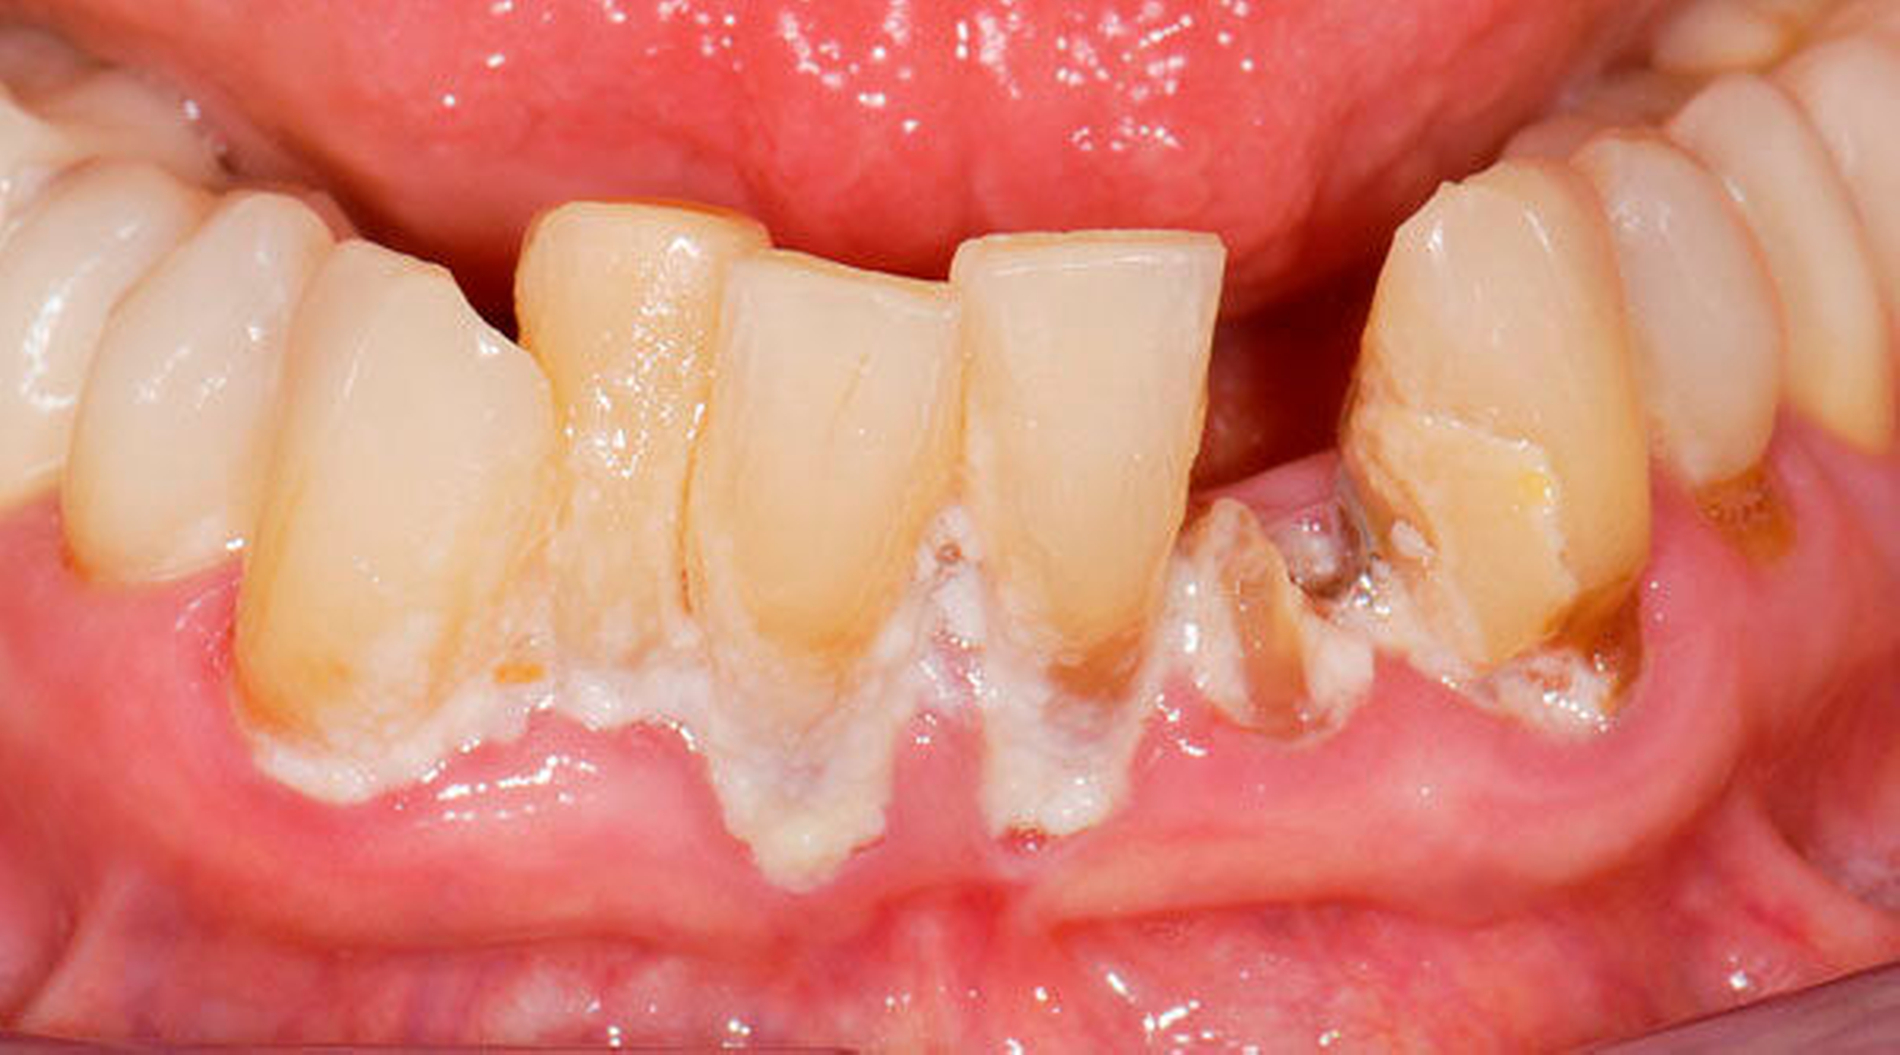

3. Restaurative Versorgungen bei Wurzelkaries

Freiliegende Wurzeloberflächen können im Alter ein locus minoris resistentiae für Karies sein. Im Zusammenspiel ungünstiger Ernährungsgewohnheiten, nachlassender Mundhygiene sowie Änderungen von Speichelquantität und -qualität kommt es zuweilen zu einem präventiv und restaurativ schwer beherrschbaren Auftreten von Wurzelkaries. Gut zugängliche Kariesläsionen können mit einphasig eingebrachtem Komposit (R1-Restaurationen) angegangen werden (Abbildungen 3 bis 5). Bei schwerer zugänglichen Arealen kommt ein zweiphasiges Vorgehen in Betracht (R2-Restaurationen). Das Vorgehen bei der R1- und bei der R2-Technik wurde mehrfach beschrieben [Frese et al., 2014a, b, c, d; Staehle et al., 2014, 2017]. Im Fall von zirkulärer Wurzelkaries sollte frühzeitig eingegriffen werden, da ansonsten die gesamte Zahnkrone frakturieren kann.

Bei älteren Patienten mit (infolge geistiger Einschränkung) vernachlässigter Mundhygiene, exemplarisch in Abbildung 5 dargestellt, wird zuweilen eine Extraktion sämtlicher Zähne vorgenommen. Eine anschließende prothetische Versorgung ist in solchen Fällen wegen mangelnder Adaptationsfähigkeit oftmals nicht mehr möglich. Dies hat zur Konsequenz, dass die Betroffenen in ihrem Aussehen, ihrer Sprachfunktion und ihrer Fähigkeit zur Nahrungsaufnahme noch eingeschränkter sind als vorher, verbunden mit vielerlei Nachteilen im psycho-sozialen Umfeld.

Wenn irgend möglich, sollte deshalb erwogen werden, einen Erhaltungsversuch wenigstens bei den gut zugänglichen Schneide- und Eckzähnen vorzunehmen, auch wenn die Prognose unsicher ist und Rezidive der Wurzelkaries zu erwarten sind. Die in Abbildung 5 gezeigte Patientin lebte zunächst noch zu Hause und wurde von einer Pflegeperson täglich betreut. Nach Umzug in ein Pflegeheim wird sie von ihrer ehemaligen Pflegerin nach wie vor ein- bis zweimal wöchentlich aufgesucht. Die Pflegerin nimmt bei ihr ein- bis zweimal wöchentlich eine Zahnreinigung mittels Zahnbürste und Interdentalraumbürsten vor, was mit einem Zeitaufwand von jeweils maximal fünf bis zehn Minuten verbunden ist. Obwohl sich nach zwei Jahren an einigen Zähnen ein Kariesrezidiv eingestellt hat, konnte der Zahnbestand gehalten werden.